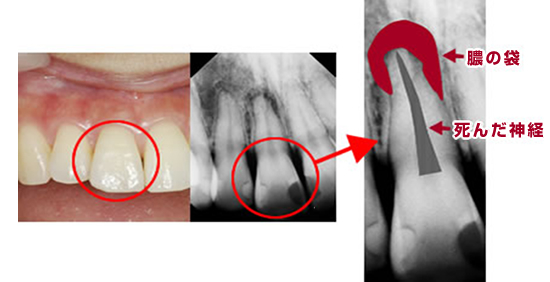

虫歯が歯の根まで達していたり、歯の根の病気にかかっている場合には、歯の中にたまった膿や死んだ神経をきれいに取り除いてあげる必要があります。

まず、歯の根の先を確認(根尖確認)してから、リーマーと呼ばれる細長い器具を使って膿・死んだ神経を取り除いていきます。